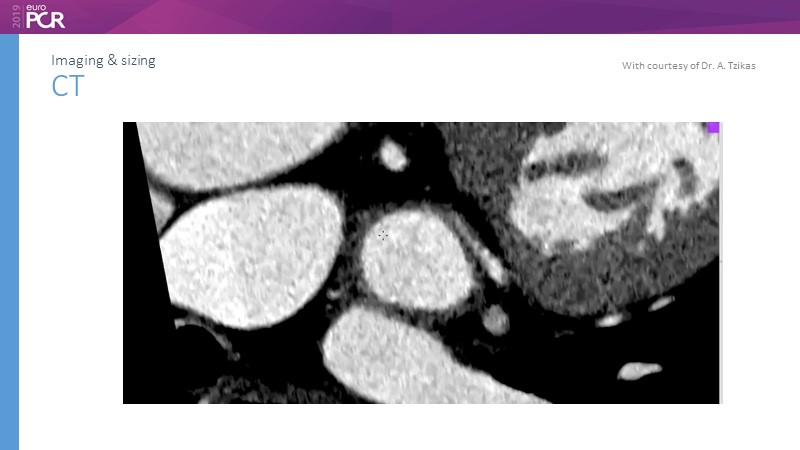

Pre-procedure planning

Previous Next